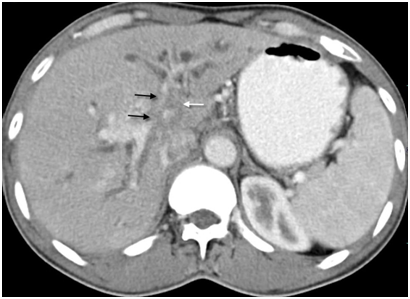

Figure 2 Coronal CT image of 68 years old male shows periductal infiltrating type II hilar cholangiocarcinoma as concentric enhancing mass in common hepatic duct involving primary confluence (white arrow).